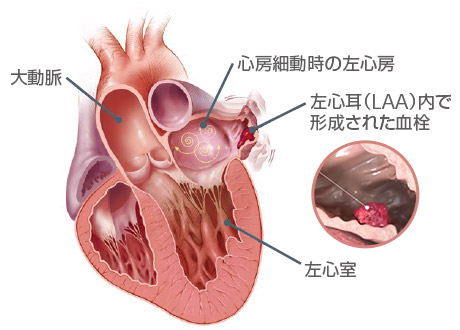

非弁膜症性心房細動の患者さんでは、脳卒中の原因となる血栓の90%以上が左心房に起始する左心耳(LAA:Left Atrial Appendage)で形成されたものです。

左房に存在する左心耳(LAA)というポケットに血栓が形成され、これが脳やほかの臓器に流れて梗塞(塞栓)を引き起こします。

心房細動は、心臓の上部にある2つの部屋(心房)が小刻みで不規則な拍動(細動)をする不整脈です。この疾患によって、心臓の左心耳(LAA:Left Atrial Appendage)に血液が滞留して血栓が形成されることがあります。血栓が動脈を通って脳に達すると脳卒中に至る場合があります。

- 非弁膜症性心房細動では、左心耳(LAA)と呼ばれる小さな袋で形成される血栓が脳卒中の主な原因と考えられています。